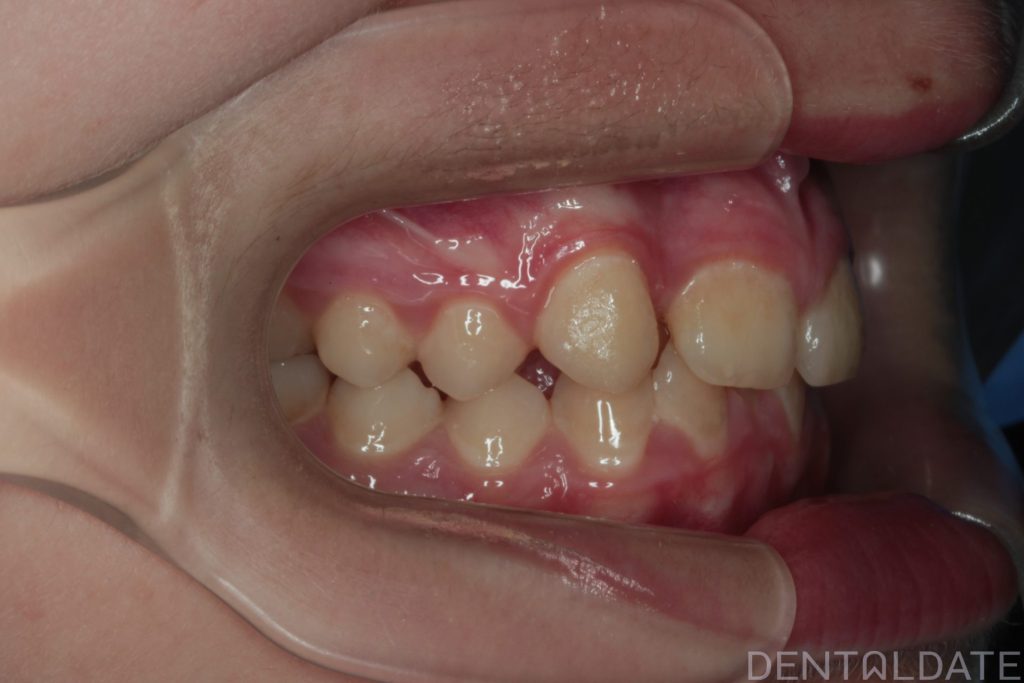

The patient presented with a complaint about an unattractive smile.

One tooth had erupted palatelly, with no space available for it in the dental arch.

The central aesthetic lines did not match, and the bite was incorrect.